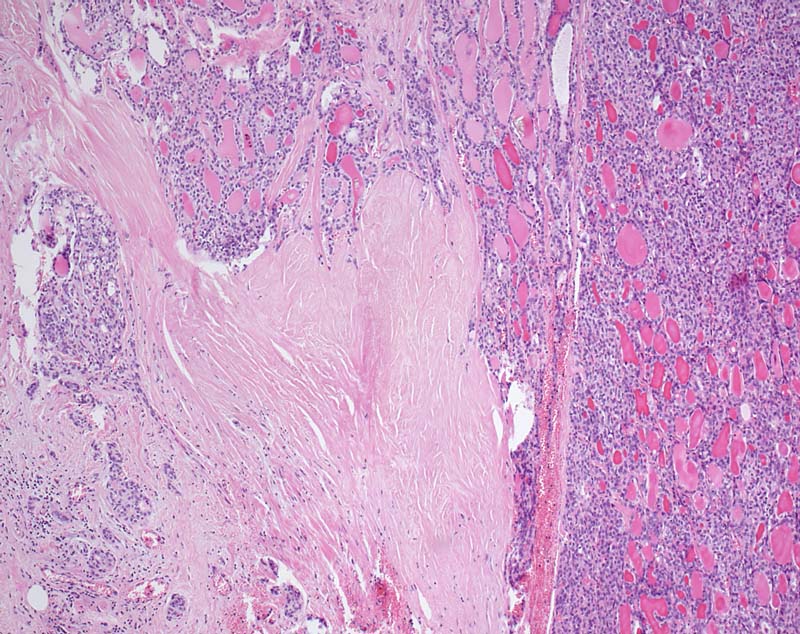

Grob invasives follikuläres Schilddrüsenkarzinom

Der follikuläre Tumor durchbricht die breite bindegewebige Kapsel.

Kapseldurchbrüche mit ausgedehnter Invasion des benachbarten Gewebes fanden sich an zahlreichen Stellen. Somit handelt es sich um ein grob invasives follikuläres Karzinom.

Follikuläre Neoplasie der Schilddrüse